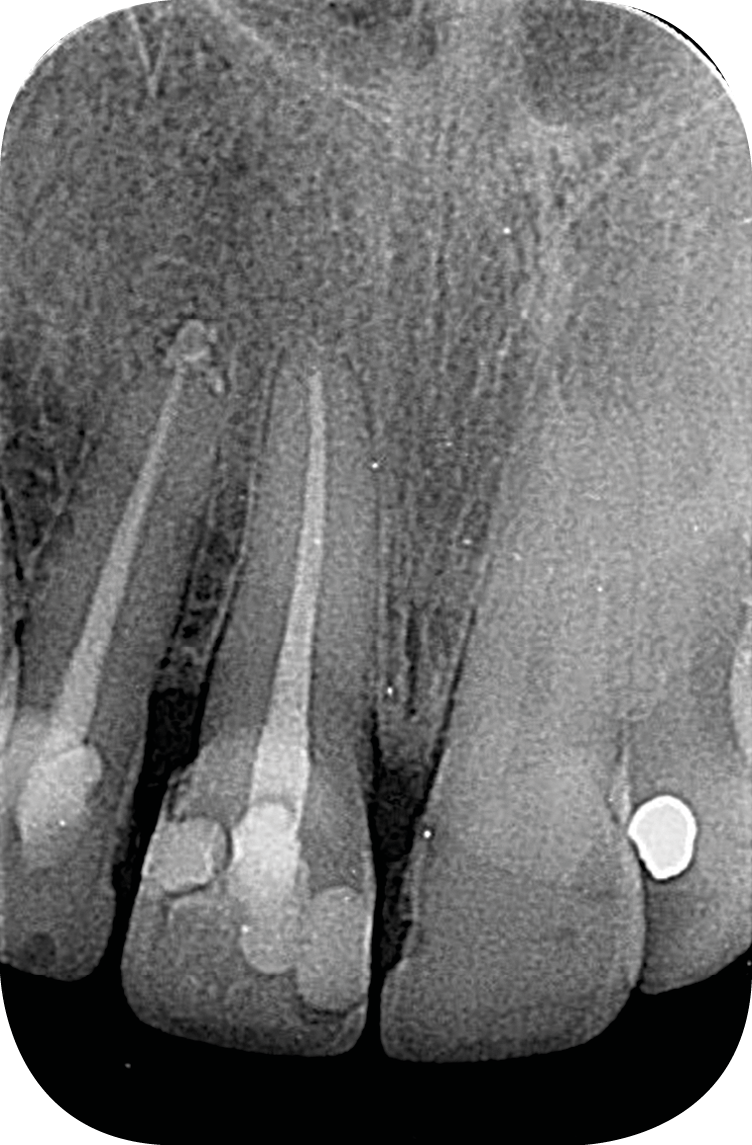

– les soins conservateurs et endodontiques [5] (fig. 4 et 5).

Les soins conservateurs et endodontiques sont majoritairement responsables des dyschromies des dents dépulpées. Nous allons développer ce point afin de mieux comprendre les paramètres régissant les colorations iatrogènes pour mieux les éviter et, si besoin, les corriger.

Ainsi, les ciments d’obturation canalaire sont la cause principale des dyschromies de la dent dépulpée [6]. Les modifications de couleur peuvent apparaître après une semaine seulement, lorsqu’il s’agit de ciments oxyde de zinc/eugénol (ZoE) [7, 8] ou à un mois post-traitement dans le cas de certaines biocéramiques [6].

Parmi les agents responsables de cette dyschromie, on peut citer l’eugénol, contenu dans les ciments ZoE et l’oxyde de bismuth, utilisé comme radio-opacifiant dans certaines biocéramiques, et principalement le MTATM [9]. L’oxyde de bismuth, quelle que soit sa concentration, même modérée dans le cas du MTA WhiteTM, provoque une coloration iatrogène de la dent en quelques semaines seulement [10] (fig. 6) [10]. Afin d’éviter ce type de dyschromies en secteur esthétique, il s’agit donc de privilégier dans notre pratique des biocéramiques qui contiennent un autre radio-opacifiant tel que l’oxyde de zirconium qui, lui, ne va pas créer de coloration iatrogène (BiodentineTM, TotallfillTM ou le BioRootTM) [11].